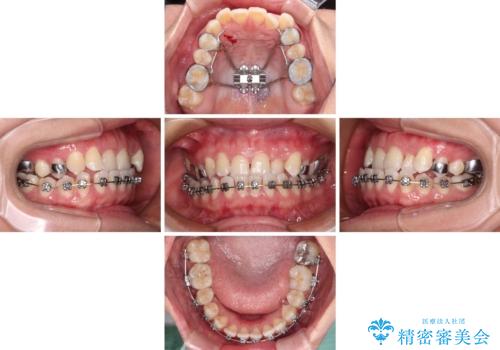

- 全顎的なクロスバイトと反対咬合を気にして来院された患者様です。

骨格的に下顎が前方位にありましたが、歯並びにより下顎が本来の位置よりも前方位に誘導される咬み合わせとなっていました。

上顎歯列および上顎骨が下顎に対して狭小であることが原因であるため、上顎の急速拡大装置を使用して上顎骨を側方に拡大することで反対咬合を改善し、ワイヤー装置で歯列を整えることとしました。

上顎の拡大に伴い反対咬合があっという間に改善されました。